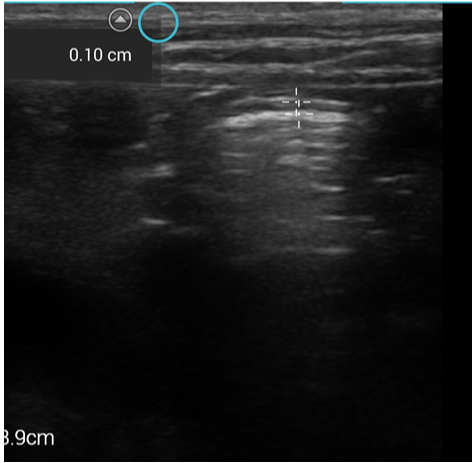

Touch screen

The touch screen is pretty intuitive if you are used to using a smart phone, and most buttons are within reach of the left thumb so you don’t need to remove the hand using the probe too frequently. However, I like to annotate my images, which means I need to take my probe hand off to type and although you can add up to 10 custom labels to each exam type, which you then can use your left hand to choose, that is not enough for me and if I am performing a full abdominal exam I am slowed by not being able to type with my left hand and removing the probe from the patient. I found that it can be tricky to make accurate measurements on a touch screen as your finger is in the way. Sonosite have thought about this though – the calipers are

marked with a cross which is surrounded by a circle – your finger only needs to be in the circle to move the caliper not directly over the cross but this does take some getting used to.

Probes

This machine has some great positives, robust, small, portable, light and quick start up time. The image quality on the linear probe is great (L38v) however with a frequency range of 10-5MHz it only reaches a depth of 9cm. The phased probe (P21v) image unsurprisingly with a frequency of 1-5MHz has less resolution, but does reach an impressive depth of 32cm. The functions are clearly labelled apart from recording a clip you have to hold the save button down for a few seconds and to change from 2D to M-mode you have to hold down the 2D button for a few seconds. Individual clips can be up to 30 seconds long.

Images from the iViz